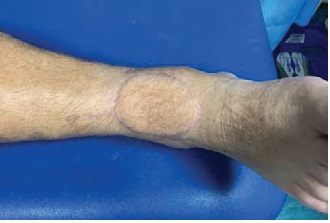

Soft tissue reconstruction, especially involving muscle, always looks bit bulky at start.

However, as the flap matures over time, its volume reduces. It usually levels with the tissue around it but can sometimes remain a bit bulky.

The colour of the flap changes over time to more or less match the skin next to it. The size and colour change is a process that takes time to settle, usually 9-12 months.

The pictures below show a timeline of a muscle flap immediately after the operation (left), after 3 months (right), and after 9 months (bottom).

Very occasionally, any bulkiness that remains can be treated, if necessary, with secondary procedures.